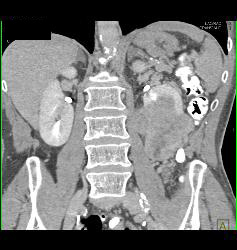

Renal Cell Carcinoma With Tumor Necrosis